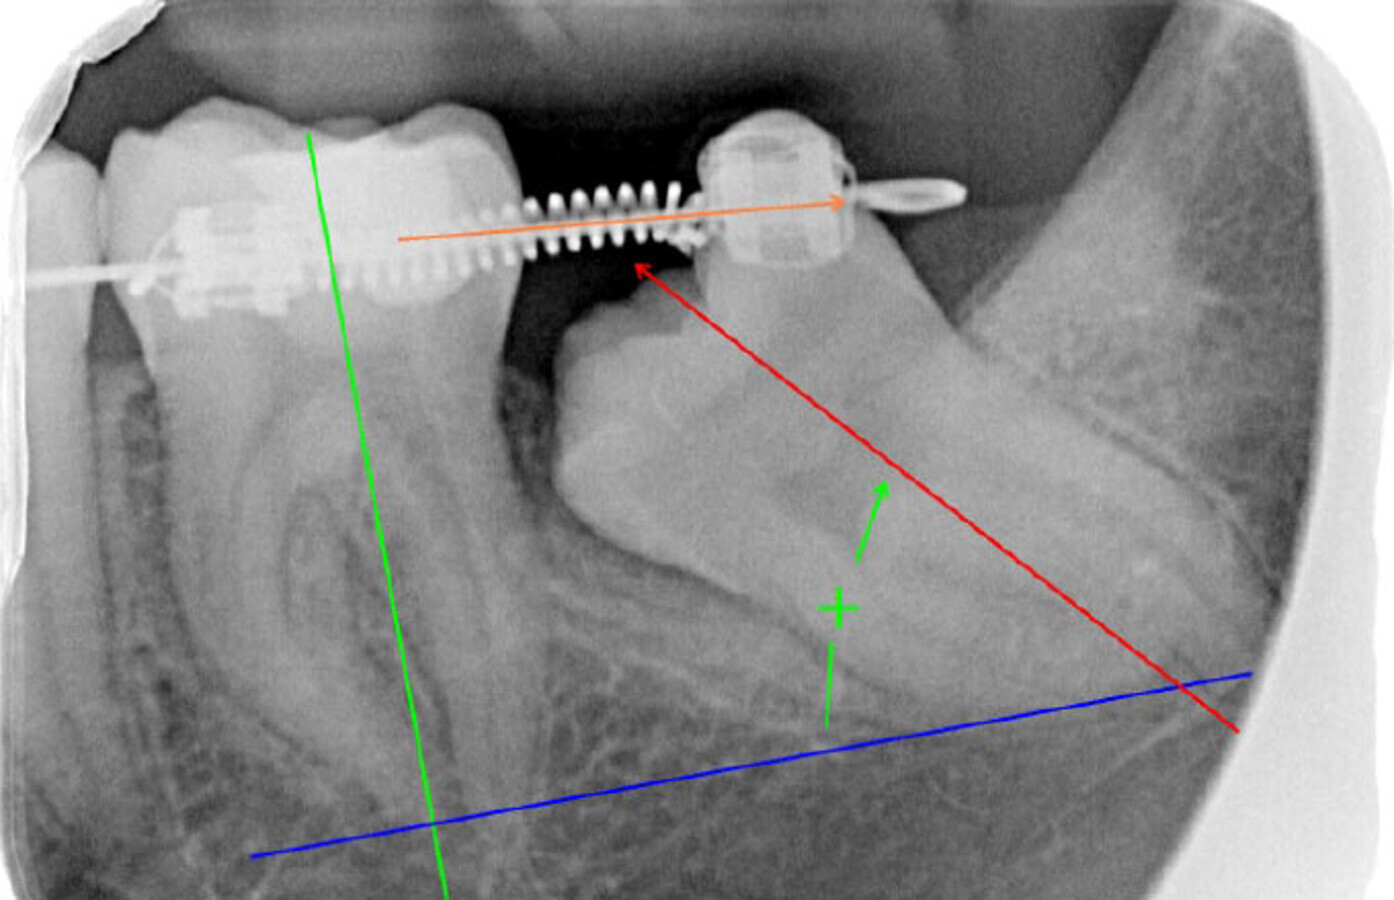

Control coil spring abierto (diente 38 exodonciado).

Planificación con tornillo de osteosíntesis.

Rx de control tracción botón (inicio).

El tratamiento ortodóntico comienza inmediatamente a la exodoncia del cordal. Como la formación de la raíz del segundo molar es completa, no se endereza quirúrgicamente (luxación). Se desimpacta parcialmente el segundo molar por medio de un coil spring abierto y un seccional NiTi de 34 a 37. Mientras tanto, va cicatrizando el alveolo y la ostectomía realizada para extraer el diente 38.

Aproximadamente 6 meses después, se prepara un anclaje esquelético con un tornillo de titanio autoperforante (D2.0 / L 12mm, Jeil Medical Corporation). Estos tornillos son más indicados para fijar injertos en bloque. Este anclaje permite enderezar el segundo molar por completo. En una primera fase, se tracciona desde el tornillo a un botón colocado en la cúspide distolingual del diente 37 con cadeneta elástica. Una vez el diente 37 está “desenclavado”, se termina de enderezar, cementando estratégicamente brackets y tubos de cementado directo y utilizando arcos elásticos NiTi.